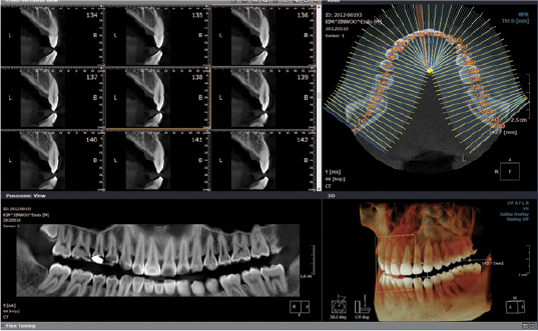

Il Tomografo Cone Beam (detto anche CBCT Tomografia Computerizzata Cone Beam) è un macchinario in grado di ottenere immagini del massiccio facciale attraverso l’emissione di una dose molto bassa di raggi X, restituendo immagini 3D di altissima qualità delle ossa mascellari e dei denti.

La tecnologia della CBCT permette di ottenere immagini precise a dimensioni reali tridimensionali e ad alta risoluzione con tempi di scansione ridotti.

La tecnologia utilizzata in questo studio utilizza nuova generazione di sensori “multifocali” Ray (by Samsung©) hanno una sensibilita? “visiva” maggiore ed una dimensione maggiore che migliora la qualita? dell’immagine con dosi raggi sempre piu? ridotte.

La CBCT ed in particolare l’apparecchio del nostro studio il Rayscan Alpha, confrontata con la CT assiale tradizionale, emette una quantità di radiazioni notevolmente inferiore (fino a 100 volte inferiore) e corrisponde a quella assorbita in circa 4 ore di volo aereo,  permettendo allo stesso tempo un’ottima risoluzione dell’immagine e una quantità di informazioni maggiori e possibilità di ripetizione dell’esame per controlli successivi a un esposizione contenuta.